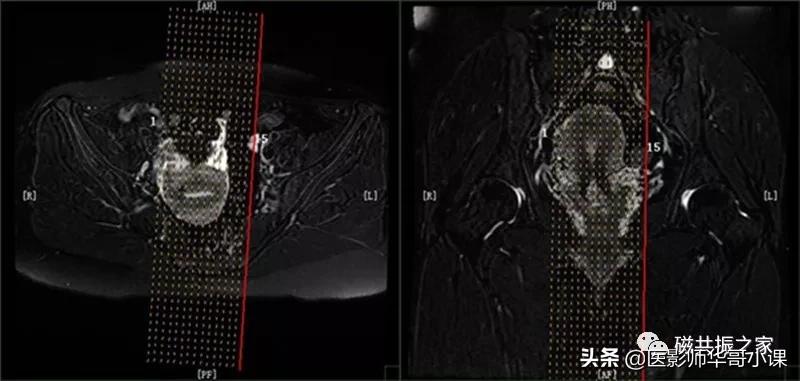

横断面: AX 3D (LAVA、VIBE、THRIVE)(动态),横断面T1加权LAVA多期动态增强扫描序列

在冠状位和矢状位上定位,扫描范围上至子宫上缘下至耻骨联合,需包括整个病变范围,如观察转移性病变需加大扫描范围。第一期蒙片扫描完成后暂停,然后注射造影剂。

在注射药物15S左右开始扫描,连续扫描8~10期。在多期扫描完成后,扫描COR 3D (LAVA、VIBE、THRIVE)及SAG 3D (LAVA、VIBE、THRIVE)序列。

在横轴位及矢状位上定位,范围包括整个子宫及病变范围。

此序列在AX 3D (LAVA、VIBE、THRIVE)扫描完成后扫描